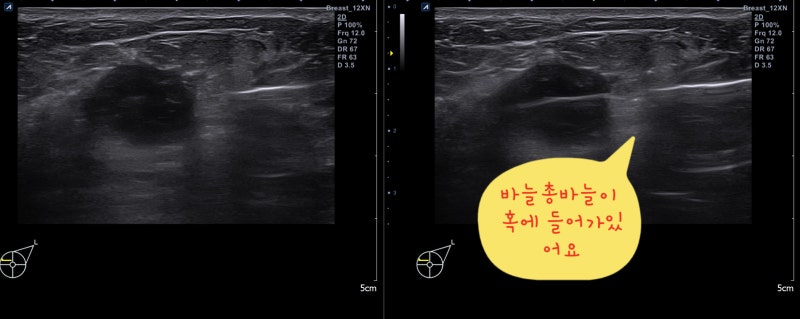

유방촬영술로 군집한 미세석회화 소견을 볼 수 있습니다. 0기 유방암 소견입니다.초기 유방암 사진유방 초음파 검사상 1cm 유방몽울입니다. 1기 유방암 진단을 받았습니다. 3 초기 유방암이 의심되는 응어리가 있을 때 조직검사유방에 혹이 진단되어 유방암인지 양성종양인지 정확한 진단이 필요한 경우 먼저 침총조직검사를 실시하십시오.젖클리닉위드심의원유방에 혹이 진단되어 유방암인지 양성종양인지 정확한 진단이 필요한 경우 먼저 침총조직검사를 실시하십시오.젖클리닉위드심의원유방침 총조직검사 동영상 접속 —> https://blog.naver.com/breastkim/221808987454유방몽울 총조직검사 <총생검> 과정 : 위드심 유방클리닉 김미혜 원장(전) 김미혜유 클리닉 원장 유방에 응어리가 진단되어 유방암인지 양성종양인지 정확한 진단이 필요하다면 먼저 침총조직검사를 해야함… blog.naver.com유방의 바늘 총 조직 검사 1. 유방 진료상 유방에 종괴이 진단되었습니다. 암입니까?유방 암의 대부분은 암이 아닌 양성 종양입니다.그러나 씨앗 덩어리 모양이 나쁘거나 크기가 커질 경우는 암을 의심하고 조직 검사를 해야 합니다. 2. 바늘 총 조직 검사는?<바늘 총 조직 검사>는 바늘을 유방 종괴에 넣어 일부 조직을 채취하는 조직 검사입니다.5개 이상의 조직을 채취해야 정확한 진단이 가능합니다.상처는 1mm정도로 거의 남지 않습니다.<바늘 총 조직 검사>는 전 세계적으로 널리 이루어지고 있는 유방 암 확진 방법으로 정확도는 99~100%입니다.3. 검사 방법 1) 누운 자세로 실시합니다.2)초음파 검사를 하면서 종륜 부위와 피부를 조금 부분 마취합니다3)바늘을 넣고 씨 덩어리에서 조직을 채취합니다. 조직을 채취할 때마다 “빵”소리가 납니다만, 통증은 없습니다. 5개 이상의 조직을 채취해야 하므로 5번 정도”빵”소리를 낼 있습니다.4)검사가 끝난 뒤 반창고나 붕대로 가슴을 닫습니다.4. 검사 시간 검사 시간은 5-10분에서 결과는 7일 이내에 전화로 알립니다.침총 조직 검사에서 꺼낸 유방 응어리 조직입니다.위 조직을 특수염색하여 현미경으로 조사하면 정확한 조직검사 결과가 나옵니다.섬유선종 특수염색 후 현미경 사진–>유방암 특수염색 후 현미경 사진 5. 검사 결과가 유방암으로 진단되면 대학병원으로 빠른 시일 내에 연결해 드리겠습니다.양성종양 진단 시 안심하셔도 되지만 *종양 크기가 큰 경우 *모양이 좋지 않은 경우 *사이즈가 커지는 종양*고위험 병변의 경우 <맘모톰 수술>을 권장합니다.유방암 진단을 받은 경우 빠른 시일 내에 대학병원으로 연계하여 치료받을 수 있도록 도와드리겠습니다.https://blog.naver.com/simjsmc/222505127069추악한 유방암에 대한 조직검사: 맘모톰 수술? 침총조직검사? : 분당위드심유방클리닉 못생긴 유방암에 대한 조직검사 : 맘모톰수술을 할까요? 침총 조직검사를 할까요? 안녕하세요 46살입니다… blog.naver.com4 초기 유방암이 의심되는 미세 석회화가 있을 때 유방조직검사미세 석회화가 모여 있을 때 <군집된 미세 석회화>라고 합니다. 이 소견의 20~30%가 0기 유방암일 수 있지만 나머지 70~80%는 양성으로 진단된다고 합니다.이를 정확하게 진단하기 위해 미세 석회화를 조직 검사하는 방법은 두 가지가 있습니다.첫 번째는 바늘 총조직 검사입니다.미세석회화 소견이 유방 초음파 검사에서 보이는 경우 <침총조직검사> 방법이 가장 좋습니다. 부분 마취 아래에 볼펜 정도의 바늘을 넣고 조직을 채취하면 되기 때문입니다.유방암의 미세 석회화 사진–>유방촬영술에서 흰 반점과 같은 미세석회화 소견이 모여 있는 군집화 미소석회화 소견입니다.유방초음파검사에서 작은 혹과 미세석회화 소견이 보입니다 침총조직검사로 조직을 채취하고 있습니다유방암으로 진단되어 <대학병원 유방센터>로 연결하였습니다.읽기용 슬라이드, 사진 등 치료에 필요한 자료를 모두 준비하여 예약해 두었습니다.두 번째는 맘모톰 수술입니다.유방석회화맘모톰수술병원위드심의원미세석회화소견이유방초음파검사에서볼수있는경우<침총조직검사>방법이가장좋습니다. 그러나 유방 초음파 검사에서 보이지 않는 경우는 맘모톰 수술을 해야 합니다.먼저 유방 촬영으로 석회화 부분에 바늘을 넣습니다.유방 촬영술로 바늘이 잘 들어가 있습니다.바늘이 들어있는 부분에서 맘모톰 수술로 석회화를 뽑아냅니다.->꺼낸 조직을 다시 유방 촬영술을 해서 석회화 소견이 나왔는지 확인하겠습니다.이 사진을 검체 촬영술 specimen mammography라고 합니다.이 사진에서 흰색 석회화 소견이 나왔는지 확인해야 합니다.0기 암 진단을 받았습니다.대학병원 유방센터로 연결해드렸습니다. 초기 유방암은 생명에 지장 없이 완치되는 아주 작은 유방암입니다.주로 0기 1기 유방암을 초기 유방암이라고 부릅니다.증상이 없는 경우가 많기 때문에 정기적으로 유방 초음파 검사를 해주셔야 진단할 수 있습니다. 검사상 이상 응어리나 미세석회화 소견이 있는 경우 <침총조직검사>를 시행하는 것이 가장 좋으며 <맘모톰수술>이 필요할 수 있습니다.분당위드심의원 김미혜원장 프로필바로가기—>분당위드심의원 김미혜원장 프로필바로가기—>